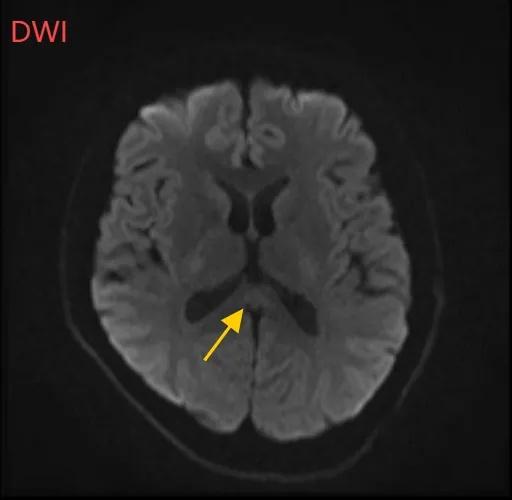

医生摇摇头,经过头部磁共振平扫、弥散、增强影像等检查,医生诊断,小董是得了一种比较少见的病症:可逆性胼胝体压部综合征。

如果把大脑比作一座城市,胼胝体就是连接左右脑的“跨海大桥”,而胼胝体压部正是桥上的“核心枢纽”。当它因酒精、熬夜或感染“肿了”,大脑信号就会“堵车”,引发一系列“故障”。

“压部”病变:胼胝体压部是大脑里的“视觉总监”,眼睛所看到的信息传送到大脑后,由它负责反应整合成图像在脑海中呈现。“压部”发生病变后,就像电视机信号接收不良,屏幕出现雪花一样,眼睛视物就会受到影响。

经过一周治疗,小董的胼胝体压部病变明显好转目前,小董已基本恢复,手不抖了,走路不晃了,记忆力和计算力也回到患病前的水平。